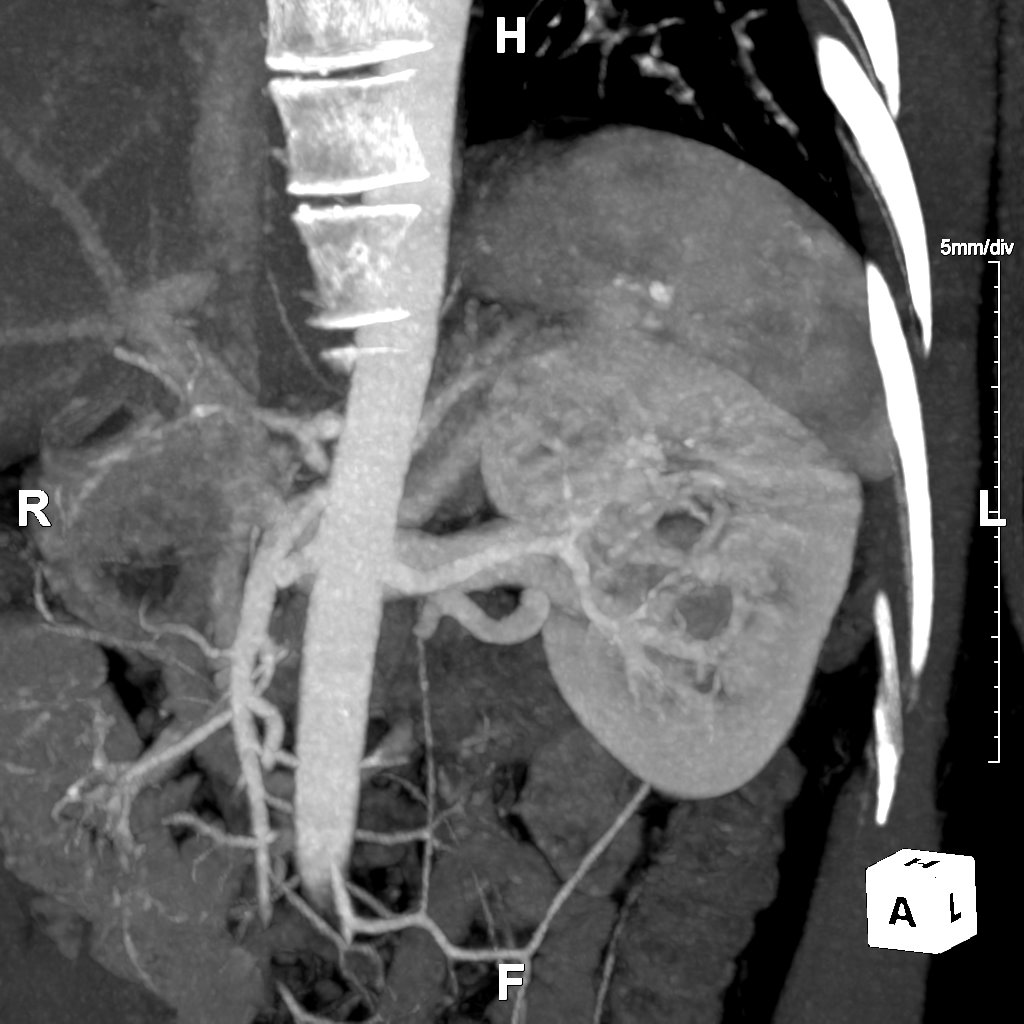

Our Routine Chest Abdomen Pelvis Service provides 3D reconstructions focusing on a thorough evaluation of the vascular system in the chest, abdomen, or pelvis. This protocol is intended for use on cases where the referring physician does not have a specialized protocol. If the patient's history is unclear, this is the default protocol for all chest, abdomen, and pelvis angiograms, or any combination thereof. Our aim for this protocol is to allow quick viewing of major anatomy and then focus only on areas of concern.

Imaging methods like Maximum Intensity Projections (MIPs) and Curved Planar Reformation (CPRs) enhance the clarity of vascular structures. MIPs are effective for visualizing blood vessels by projecting the highest attenuation values onto a 2D image, while CPRs offer detailed views along the natural curves of the vessels, aiding in the detection of abnormalities and enhancing diagnostic accuracy.